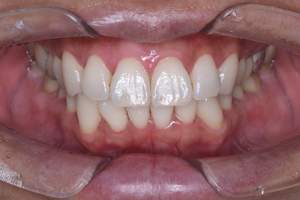

歯石除去

治療前

治療後

| 年齢 | 43歳・男性 |

| 主訴 | 歯石をとりたい |

| 治療内容 | 歯石除去 |

| 治療期間 | 30分 |

| 費用 | 約2,000円 |

| リスク・副作用 | ・歯ぐきの炎症が強いと歯石を取る際に出血することがあります ・処置後に歯がしみることがあります ・歯と歯の間に隙間ができるので、息が漏れ発音しにくいと感じることがあります ・歯ぐきの炎症が軽減すると歯ぐきが引き締まり、歯が長く見えることがあります |